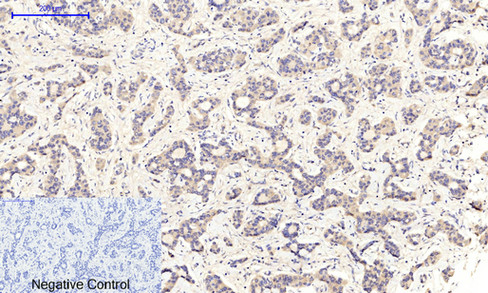

Immunohistochemical analysis of paraffin-embedded Human liver cancer tissue using MEK1/MEK2 Antibody.Negative control was used by secondary antibody only.